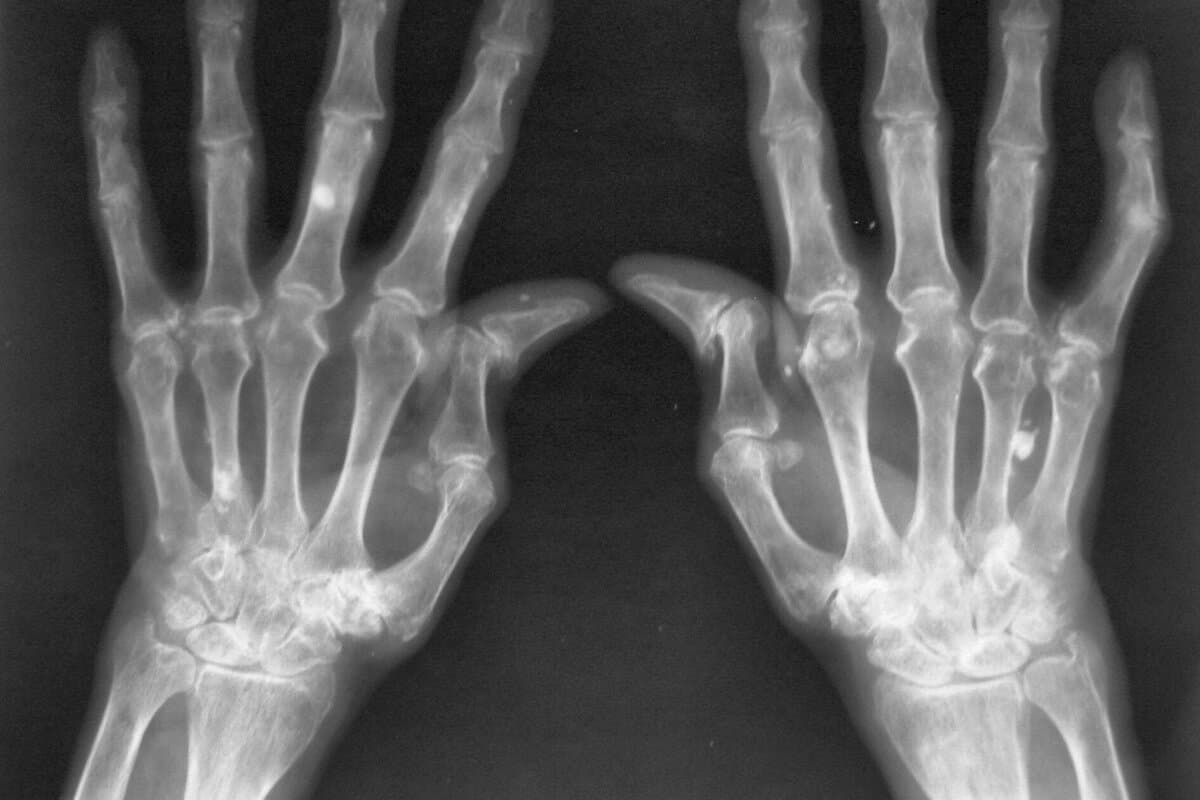

Prognose der frühen rheumatoiden Arthritis

Die röntgenologischen Gelenkschäden wurden in der Studie mit dem SvdH-Score erfasst. Über alle Kohorten hinweg war dieser Score in den mild-inflammatorischen Gruppen niedriger als in den autoimmun-inflammatorischen. Mit anderen Worten: Patienten mit früher Arthritis, die erhöhte Entzündungswerte und Autoantikörper aufwiesen, entwickelten häufiger radiologische Schäden als Patienten ohne diese Marker.